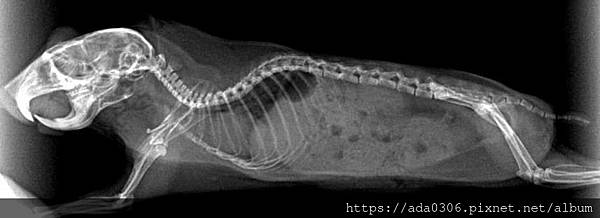

圓呼呼的團團,非常不配合照X光,所以讓她吸一口麻醉睡了幾秒,一拍完就自動醒過來了,時間抓得剛剛好。

在其他項目的檢查中,團團各部位都正常,除了有駝背。X光下顯示出許多老化跡象,還好有提早發現,表示老年健檢是很重要的!

這張刻意拍到頭部,團團的臼齒有缺角,應該是蛀牙,醫師說如果發現她吃東西會痛或不舒服,建議提供磨碎的飼料。

心臟有變大,應該是左心房,反映出心臟功能變弱,目前不用投藥,但建議補充心臟保健品。

脊椎的椎間盤有三四節已經退化黏在一起了,那部份就不能彎曲,走路會僵直,這也是駝背的原因。

腎臟與肺臟的尺寸正常無腫大,團團雙腿膝蓋也是退化性關節,肚子內有食物和一些空氣,應該是吃東西時一併吞下的。